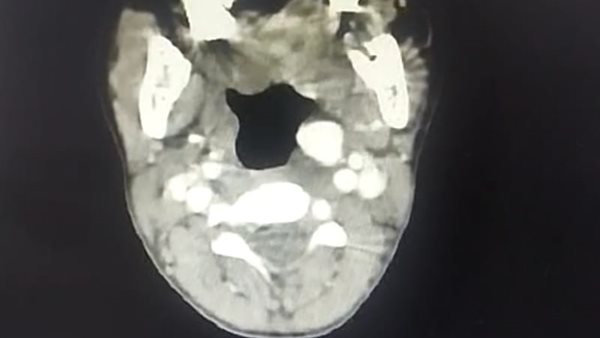

فريق طبي بجامعة أسيوط ينقذ بصر طفل يعاني من وجود خراج خطير بالعين

فريق طبي بجامعة أسيوط ينقذ حياة طفل من الموت لإصابته بنزيف حاد عقب استئصال اللوزتين